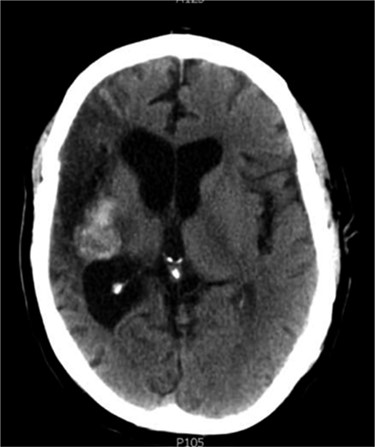

Between 2005 and 2012, the clinical condition remained stable and there were no significant radiological changes identified (Fig. 2). In July 2012, the patient re-presented with worsening left sided weakness and a left sided homonymous hemianopia. CT scan at this time demonstrated a 4 × 4cm well-defined mass of CSF density in addition to the pre-existing lesion in the right external capsule. Neither enhanced with contrast and there was no significant midline shift. An MRI head showed the lesion to contain a significant solid component. It appeared somewhat vascular and there was suspicion that it could represent a low-grade tumour (Fig. 3). The patient underwent a right-sided craniotomy to remove the mass.

Axial CT head (2007) demonstrating hyper-dense cystic abnormality in the right external capsule.